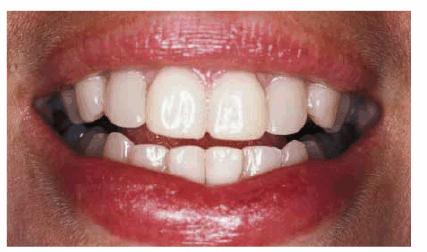

PROBLEM: This 38-year-old store owner presented with crowded and

discolored maxillary and mandibular teeth (Figures 24-7A, and 24-7B). Although orthodontic treatment was suggested as ideal

treatment, he elected a compromise that consisted of bonding the mandibular and

crowning the maxillary teeth.

Figure 24-7A: This 38-year-old man wanted to improve his crowded maxillary and mandibular teeth.

Figure 24-7B: This occlusal view shows why full orthodontic treatment was originally presented as the ideal treatment. The patient insisted on a "quick fix" solution.

RESULT: The resulting smile with straighter and lighter teeth (Figures 24-7H, and 24-7I) was most appreciated by the patient.

Figure 24-7H: Pretreatment smile.

Figure 24-7I: Post-treatment smile with six maxillary full porcelain crowns and four mandibular incisors with bonded composite resins.